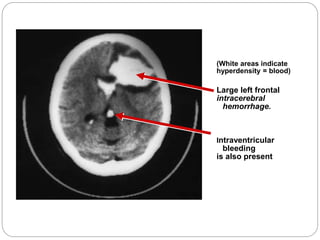

(White areas indicate

hyperdensity = blood)

Large left frontal

intracerebral

hemorrhage.

Intraventricular

bleeding

is also present